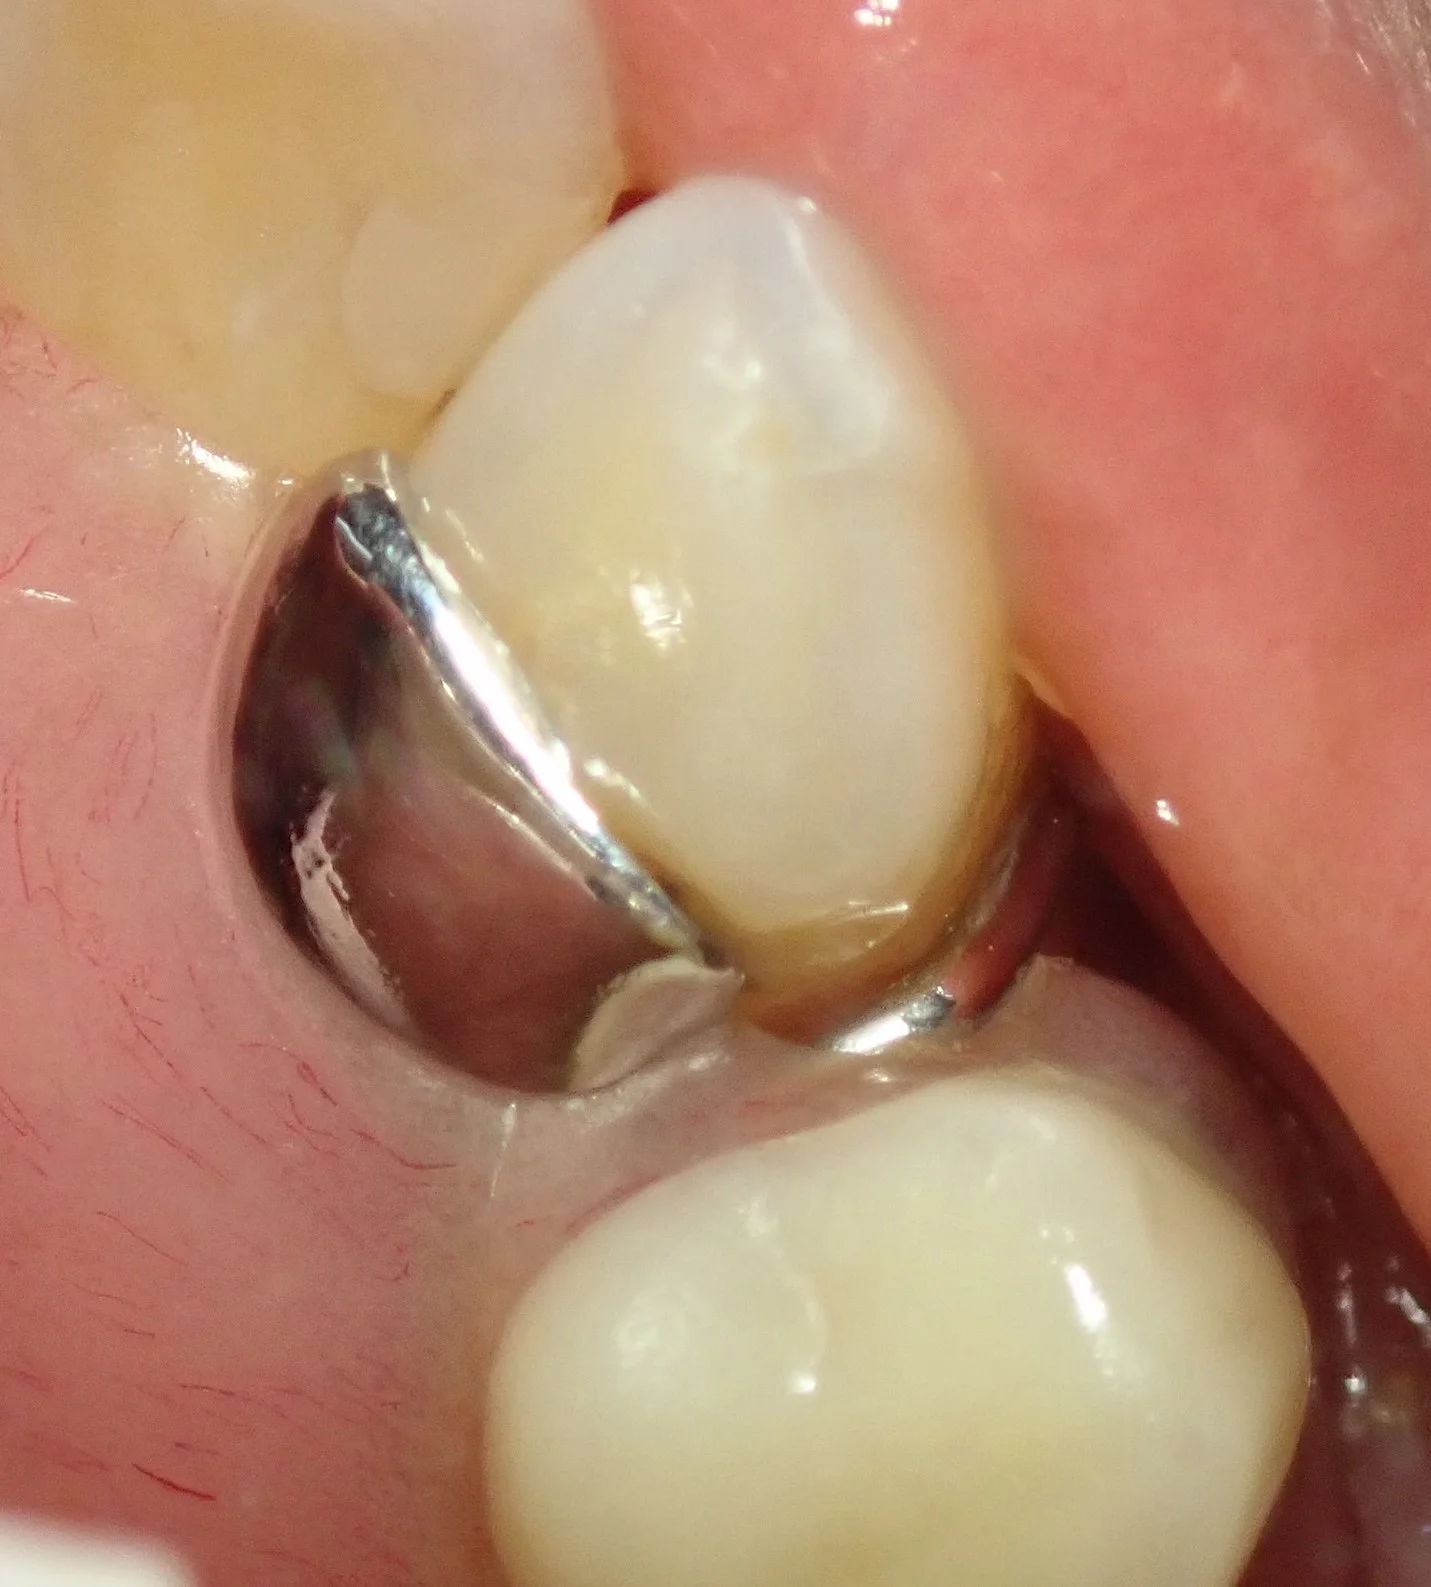

義歯のクラスプ(針金)が掛かっている歯です。

この部分は汚れが一番溜まりやすいため、義歯を入れている方は最も虫歯や歯周病になりやすくしっかりとケアする必要があります。

で、そのまま研磨して、元の義歯を装着すると

こんな感じで、ぴったり隙間なく綺麗に詰めることが出来ますヽ(゚∀゚)ノ パッ☆